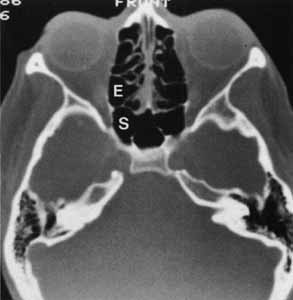

Fig. 4 Axial computed tomography demonstrating the ethmoid (E) and sphenoid (S) sinuses. (Courtesy of June M. Unger, MD, University of Wisconsin.)

As mentioned previously, the ethmoidals are the most exuberant growing sinuses and may pneumatize the frontal, sphenoid, palatine, and lacrimal bones. The ethmoid sinuses are shaped like a box slightly wider posteriorly where it articulates with the sphenoid (see Fig. 4). The anterior and middle ethmoidals drain into the middle meatus, whereas the posterior cells may drain into the superior meatus. The roof of the orbit slopes down as it travels medially, and this slope continues at the frontoethmoidal suture to become the ethmoid roof (fovea ethmoidalis), and finally to overlie the nasal cavity as the cribriform plate. The crista galli bisects the cribriform plate above and continues below as the vertical nasal plate (vomer). Three to fifteen air cells expand from each lateral border to the cribriform plate, and the air cell masses convolute medially to form the middle, superior, and supreme (if present) turbinates. The surgeon should be aware of the anatomic relationship of anterior ethmoid air cells to the lacrimal sac fossa when performing external dacryocystorhinostomy. Blaylock7 evaluated computed tomographic scans of 190 orbits with normal ethmoid anatomy and found that in 93% of the orbits, the cells extended anterior to the posterior lacrimal crest, with 40% entering the frontal process of the maxilla.